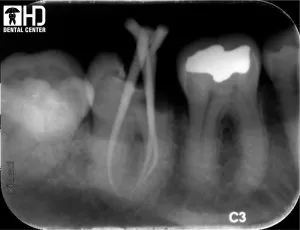

3/ Chữa tủy xuyên qua mão răng

Bệnh nhân có một cầu răng sứ 4 đơn vị ( từ răng 48 đến răng 45 ). Vì tình trạng cầu răng còn tốt, nhưng răng 48 bị viêm tủy gây đau, chúng tôi đã quyết định chữa tủy xuyên qua mão răng để giữ lại cầu răng cho bệnh nhân

Răng 48 là răng khôn hàm dưới, ở vị trí sau nhất của hàm răng, trường hợp này răng 48 còn bị nghiêng gần, và phải chữa tủy xuyên qua mão răng sứ, nên đây là một ca khá khó khăn. Sử dụng trâm Wave-one, chúng tôi đả đạt được kết quả điều trị tốt